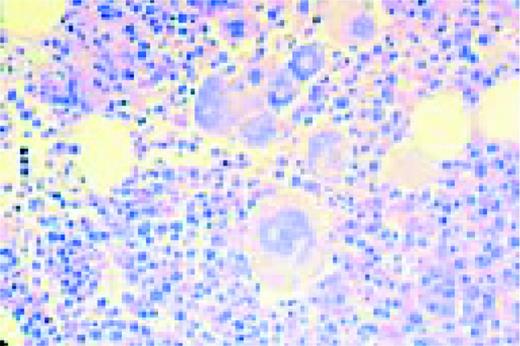

Slide L44

Multiple myeloma, bone marrow biopsy, Giemsa stain. There is complete replacement of the normal marrow by neoplastic plasma cells. These again are recognized primarily by their nuclear eccentricity.FIG44